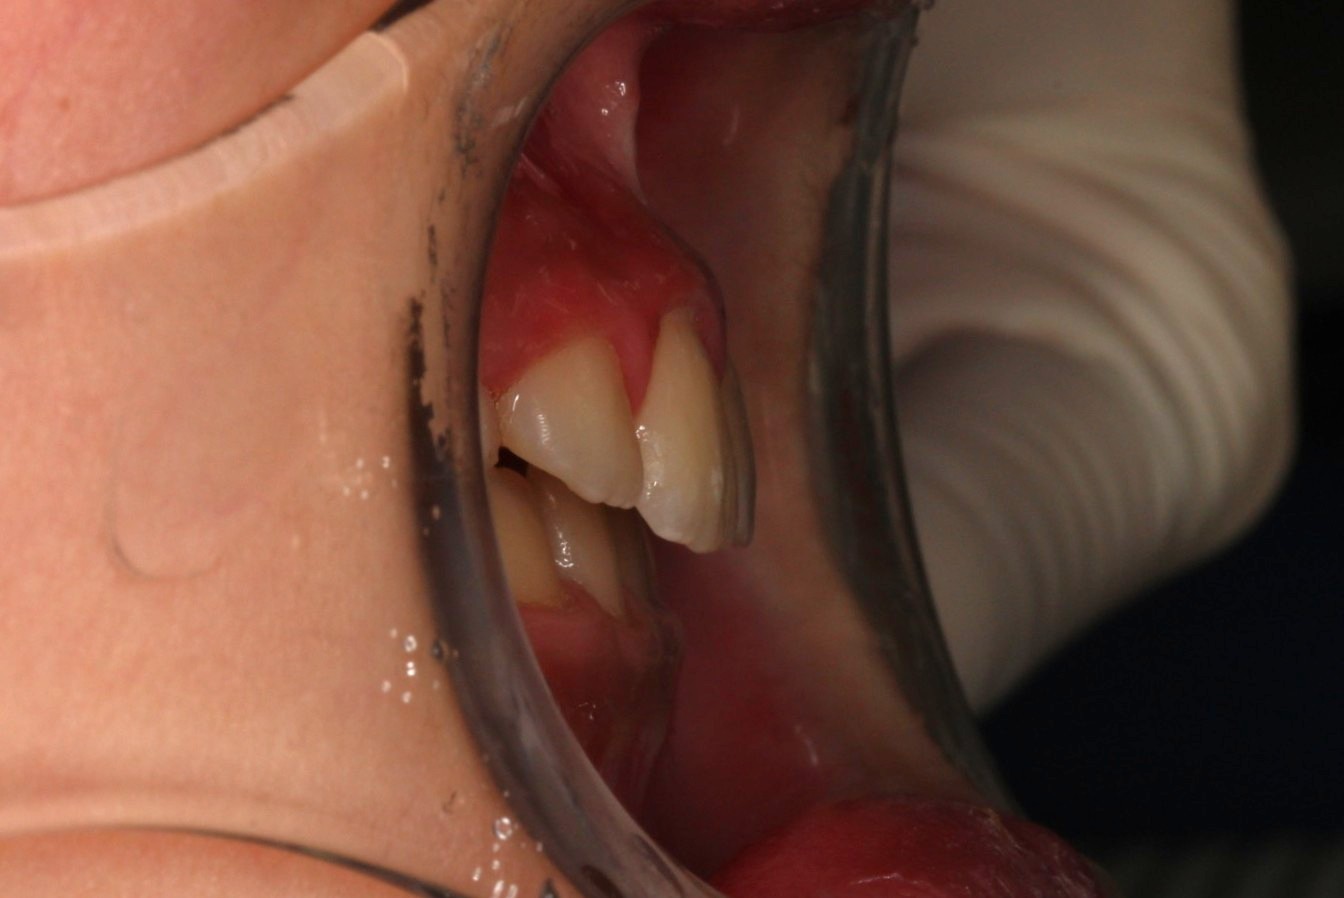

矯正術前:右側

矯正術前:オーバージェット